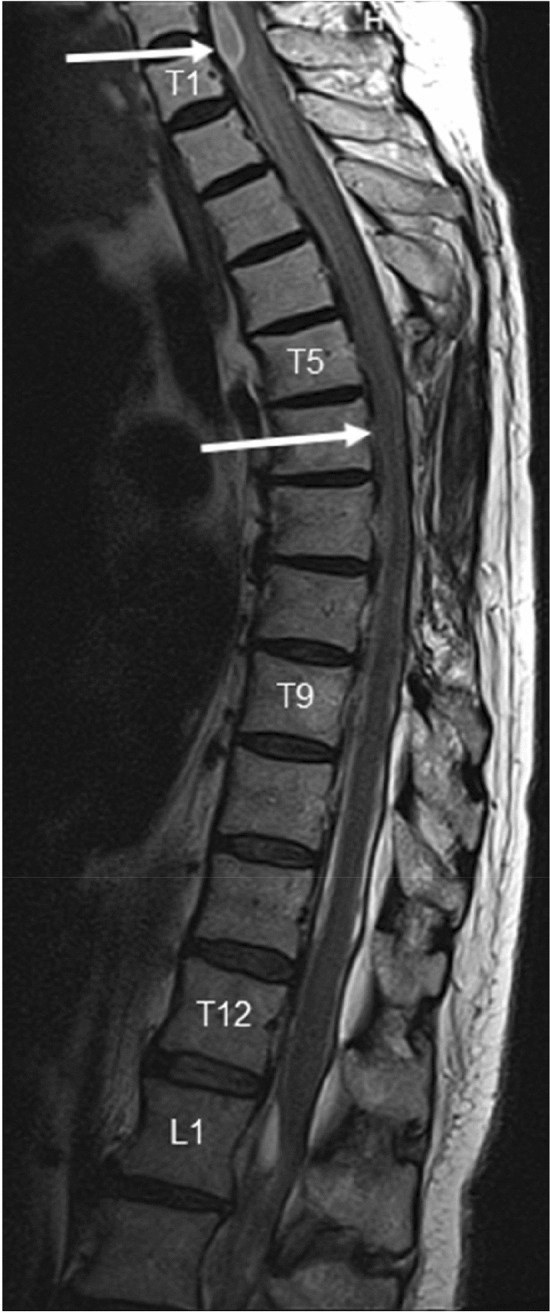

Neurological examination on admission showed spastic paraparesis with the muscle strength of 2–3 on Lovett scale and decreased superficial sensation at T4–T5 level. The MRI of the thoracic and cervical spine showed spinal cord and thecal sac deformity at the T2–T3 level caused by arachnoid adhesions with a coexisting 4-cm-long lesion of spinal cord extending from the upper edge of the T2 vertebral body down to the upper part of T4 vertebra as well as reduction of perispinal fluid reservoir from T4 down to T9 and from T12 down to L1. Strict adherence of the spinal cord to the spinal canal was noted (Fig. 1). Based on this MRI results a diagnosis of adhesive arachnoiditis was made. The patient did not meet criteria for neurosurgical intervention. She was treated with corticosteroids with no effect. The patient was transferred to Rehab Unit but she presented no improvement of motor function after physiotherapy—on the day of discharge the patient was wheelchair-bound.

Fig. 1.

a MRI T2-weighted STIR-sagittal view of spine, b MRI T2-weighted STIR-transversal view of spine Arachnoid adhesions in spinal canal of the upper thoracic and lower cervical spine. Spinal sac and spinal cord deformities. Strict adhesion of the spinal cord to the front wall of dura mater at the Th2–Th3 level with a coexisting malacia